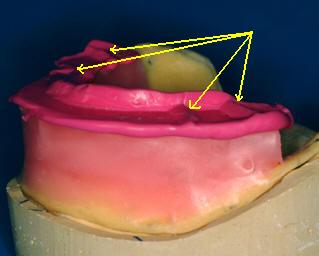

5-Determinar la relación maxilo-facial con arco

facial anatómico y la posición de relación céntrica mandibular.

- Usted a marcado sobre el rodete superior la

posición de las líneas caninas.

- Realice escotaduras en "V" en el rodete

inferior y superior de 3 a 5 mm de profundidad; siempre de tras de las marcas

de las guías caninas. (Ver imagen inferior)

El

material no debe desbordar los rodetes |

Registro en céntrica

con silicona para registro |